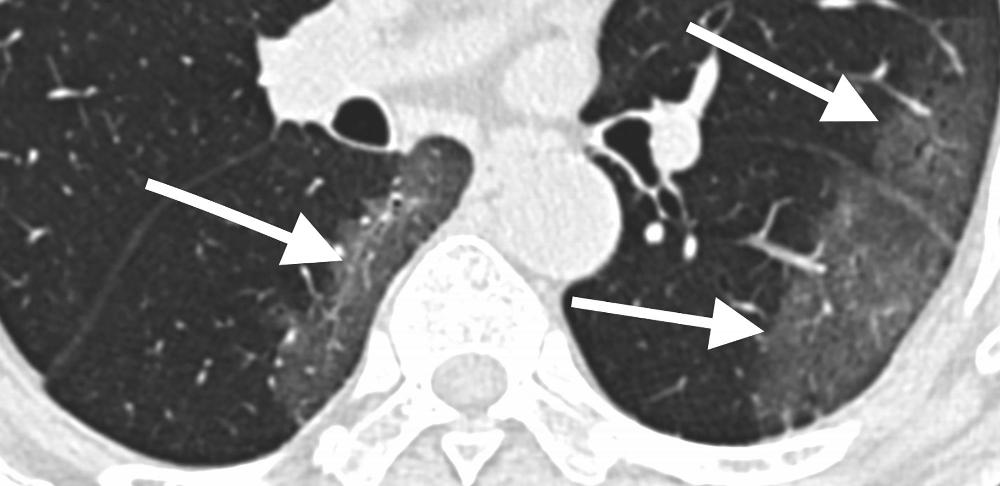

Figure 1. 29-year old male with unknown exposure history, presenting with fever and cough, ultimately requiring intensive care unit admission. (a) Axial thin-section non-contrast CT scan shows diffuse bilateral confluent and patchy ground-glass (solid arrows) and consolidative (dashed arrows) pulmonary opacities. (b) The disease in the right middle and lower lobes has a striking peripheral distribution (arrow).

Figure 4. 69-year old male with history of recent travel to Wuhan, presenting with fever. Axial thin-section non-contrast CT scan shows ground-glass opacities in the lower lobes with a pronounced peripheral distribution (arrows).